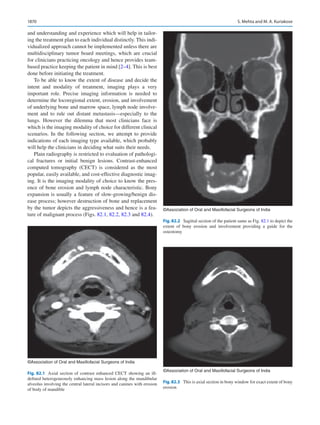

Autoimmune disorders

PT (for warfarin)

PTT (for heparin)

Repeated on the evening before/morning of the surgery to document normal coagulation parameters after